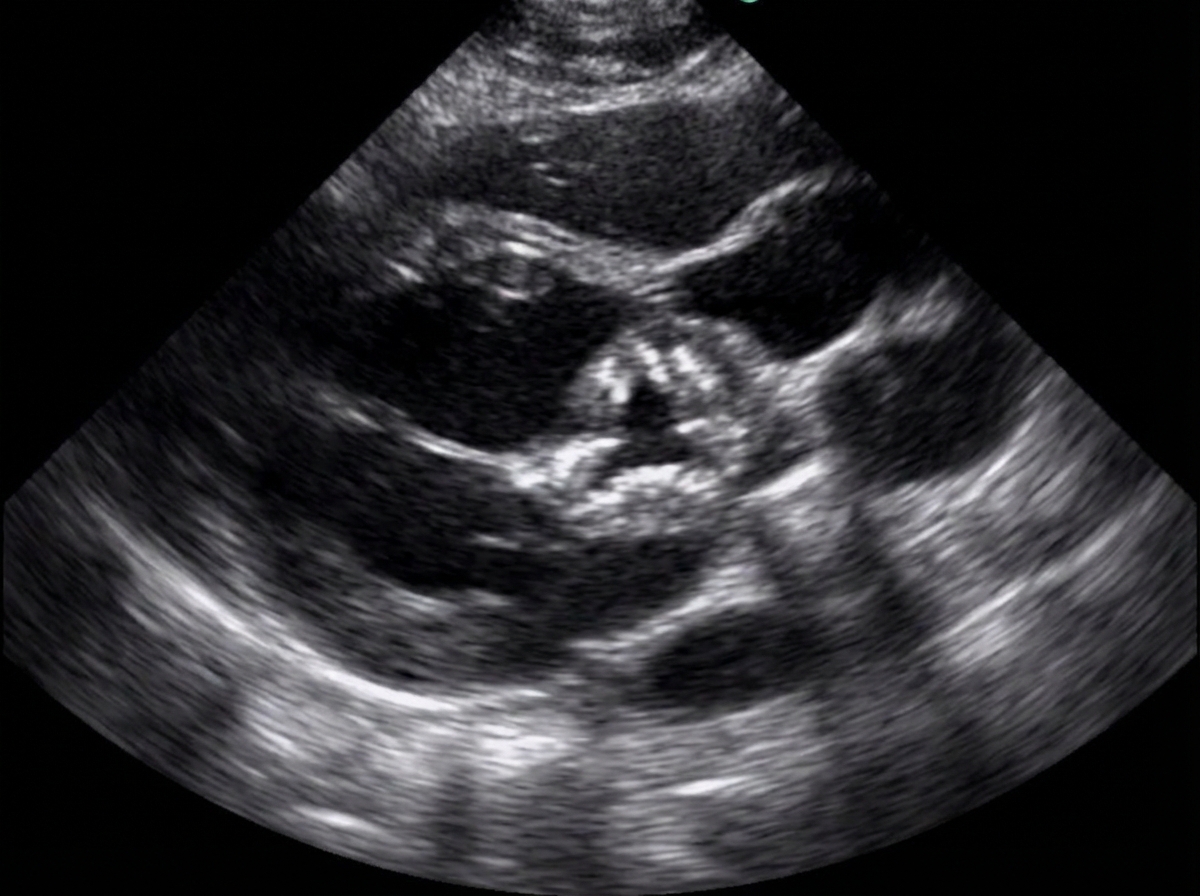

A 38-year-old woman presented with shortness of breath and fatigue. Her history is unremarkable except for a vague history of fever and joint pain as a child. She notes some recent fatigue and difficulty in sleeping that she attributes to job-related stress. On examination, her heart rate is 120 beats/min. Echocardiogram revealed the following finding. Auscultation of the heart indicates a harsh systolic murmur during left ventricular ejection. Which of the following pathological findings is not related with the underlying etiology?

Explanation: ***Pulmonary hypertension*** - **Pulmonary hypertension** typically results from elevated **left atrial pressure** due to **mitral stenosis**, not aortic stenosis. - **Aortic stenosis** primarily causes **left ventricular pressure overload** without directly affecting pulmonary circulation. *Aortic regurgitation* - **Rheumatic fever** commonly affects both **aortic** and **mitral valves**, causing mixed lesions including **aortic regurgitation**. - **Bicuspid aortic valve** from rheumatic disease can lead to both **stenosis** and **regurgitation** over time. *Left ventricular hypertrophy* - **Aortic stenosis** causes **pressure overload** on the left ventricle, leading to **concentric hypertrophy**. - **LVH** is a direct compensatory mechanism to maintain **cardiac output** against increased **afterload**. *Mitral stenosis* - **Rheumatic fever** classically causes **mitral stenosis** through **commissural fusion** and **leaflet thickening**. - **Mitral stenosis** is the most common **rheumatic valvular lesion** and often coexists with **aortic involvement**.